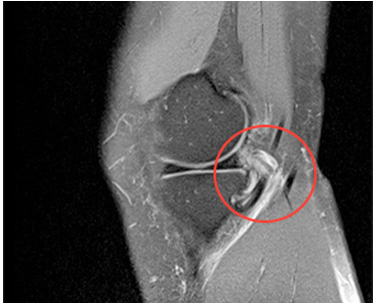

▶ 갑작스런 운동이나 충격으로 힘줄 주변에 물혹이 생긴 상태 (MRI)

검사 / 진단

진찰로 진단이 가능하며, 너무 심한 경우 초음파,

MRI 등을 권하게 됩니다.